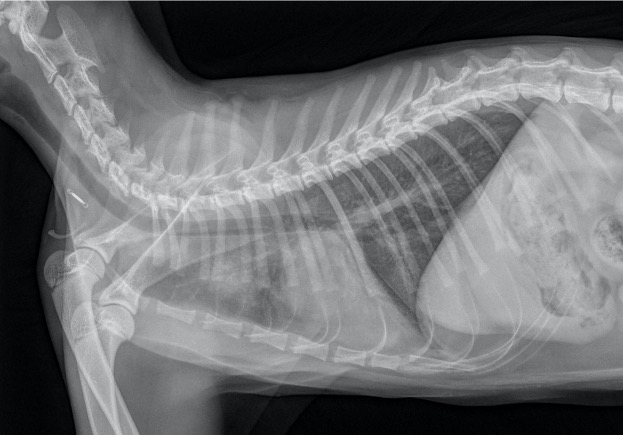

Les radiographies thoraciques (Images 1 et 2) montrent une opacification pulmonaire interstitielle généralisée. Des foyers alvéolaires mal délimités dans le lobe crânial droit et le lobe moyen droit masquent une partie de la silhouette cardiaque. Les vaisseaux pulmonaires sont épaissis. L’ensemble de ces éléments orientent vers un œdème pulmonaire cardiogénique.